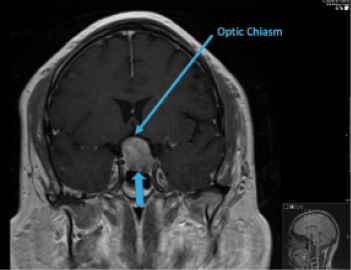

I thought that the changes in this patient’s visual acuity could be attributed to bilateral cataracts. The inferior nasal step in his left eye appeared to be localized to the RNFL. The other visual field changes respected the horizontal meridian, however, and seemed out of proportion to the RNFL damage. I ordered an MRI of the brain with and without contrast and subsequently referred this patient to neurosurgery for treatment based on findings of a pituitary mass (Figures 3–5). He subsequently underwent resection of the mass (Figure 6).

Figure 3. T1-weighted MRI scan, coronal section, with contrast. Blue arrow indicates the growing pituitary mass.

Figure 4. T1-weighted MRI scan, coronal section, with contrast. Blue arrow indicates the growing pituitary mass. Labeled elongated blue arrow indicates the optic chiasm.